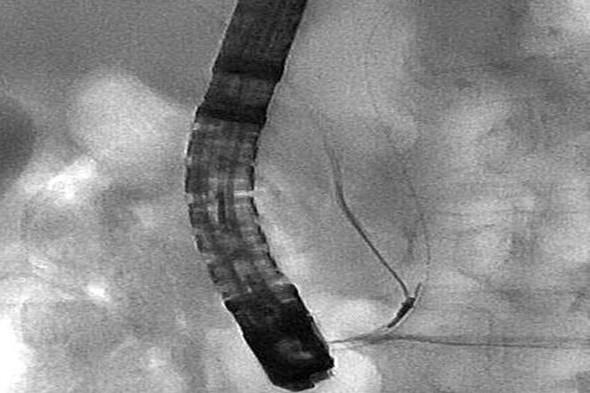

李大娘的病情还真挺平稳,31日下午,李大娘第5次来到了介入手术室,患者满面踌躇,复杂的心境不言而喻。两个科室的联合手术开始了,患者在仰卧位下,刘主任和莫大夫的介入团队通过导管先把导丝送入至主胰管,一边将患者转换成俯卧位一边看护着导丝。消化科团队接着跟上,陈主任沉着娴熟的操控内镜,护士邵月春、范莹密切配合,在十二指肠镜下将另一根导丝插入主胰管,再通过这根导丝送入网篮。刘主任开始进退从胆总管进入胰管内的导丝,把导丝头端送入网栏内。当陈主任把胰管内的导丝慢慢拉出到十二指肠的那一刻,大家欣喜若狂,终于成功对接了!进一步的内镜取石过程尽管还有周折但最终结石还是取了出来,整个手术结束已经是16:00。

内镜下取出进入胰管的导丝

两个团队对接成功